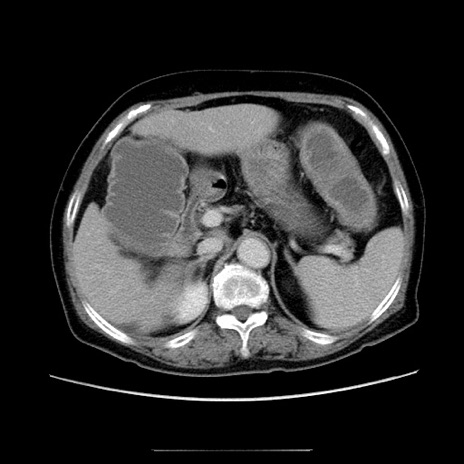

症例5(横断像)

【症例】70歳代女性

【主訴】お腹が張る

【現病歴】1週間くらい前から腹部膨満の自覚あり。昨日夜から増悪したため、本日救急外来受診。

【身体所見】意識清明、BT 36.5℃、BP 165/106mmHg、HR 80bpm、SpO2 98%、腹部:膨満、軟、自発痛・圧痛なし、触診にて不快感あり、腸蠕動音:減弱

【データ】WBC 12600、CRP 1.04